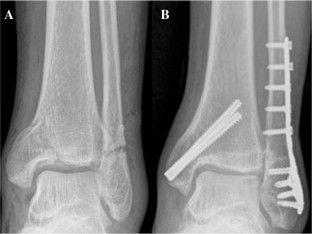

Fig. 1

Fig. 2

Fig. 3